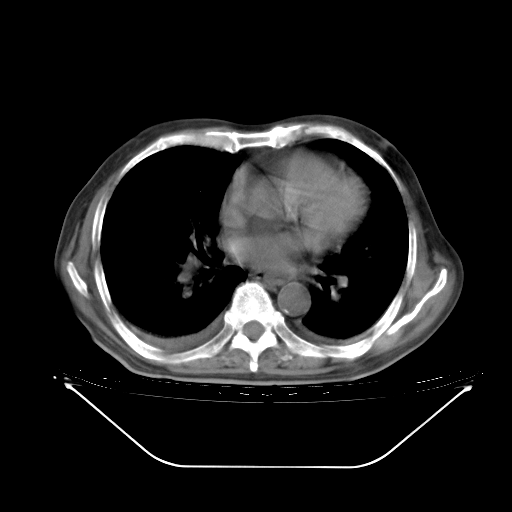

胸腹部CT,诊断意见:左上肺叶钙化灶、左侧胸膜局限性增厚并钙化、胆囊炎。描述部分肺组织呈磨玻璃样改变。